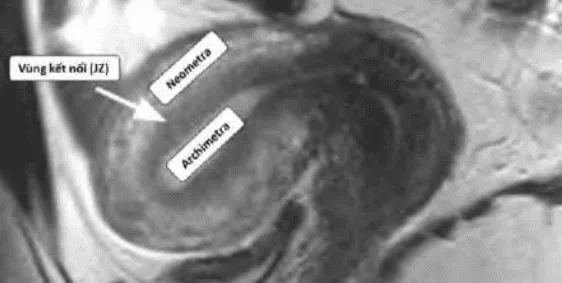

Hình ảnh “Cộng hưởng từ của adenomyosis”.

Thuyết tử cung hai nguồn gốc: Tử cung phát triển từ hai nguồn Muller và trung mô, gặp nhau tại vùng kết nối (JZ). Adenomyosis xuất phát từ chồng lấn bất thường tại JZ.

Hình ảnh “Tử cung bình thường trên MRI”.

Hình ảnh “Adenomyosis trên MRI”.